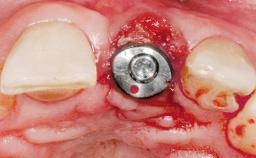

A 30-year-old female patient was referred to the office for the treatment of tooth 11. Her chief concern at the initial visit was to inquire, “Why is my tooth pink?” Upon clinical examination, it was determined that tooth 11 had a previous history of trauma and that the clinical crown had become noticeably pink in color as a result of internal resorption. This diagnosis was confirmed radiographically, indicating a large radiolucency involving the central and distal portions of the clinical crown. It was determined that restoration of this tooth was not possible, and that extraction was indicated. The presence of a mid-line diastema, which the patient wanted to reproduce, directed the treatment plan for tooth replacement utilizing a dental implant.

Bone Augmentation Horizontal|Simultaneous

Augmentation Materials Autogenous chips|Membrane

Placement Protocol Immediate implant placement

Socket Integrity Sufficient, with intact bone walls

Bone Volume Sufficient, with intact walls